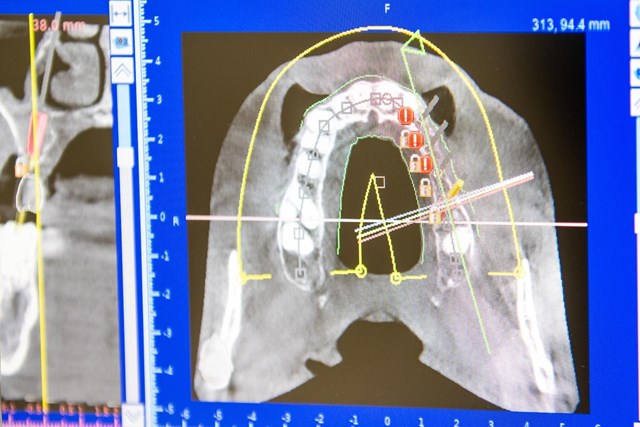

Para los casos que requieren una planificación detallada, utilizamos cirugía guiada por ordenador y TAC, para colocar los implantes de manera correcta y garantizar la rehabilitación protética que sustituirá los dientes perdidos. Contáctanos si quieres más información.

Antes de comenzar cualquier tratamiento de implantología dental en Pontevedra, las odontólogas de Sorrisos estudian de manera personalizada el caso del paciente y planifican, de manera minuciosa, los pasos a seguir para obtener el mejor resultado.

Trabajamos a través de la cirugía guiada, lo que nos permite, de forma asistida a través del ordenador, planificar la posición y distribución tanto de dientes como de implantes, tipo de cirugía necesaria en cada caso particular... y, por lo tanto, conseguir la máxima precisión a la hora de colocar cada implante dental. Reserva una cita para un primer estudio.